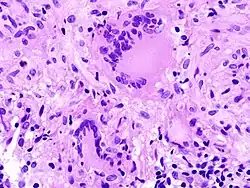

- Fremdkörper-Riesenzellen - Typisch in Fremdkörpergranulomen, die Zellkerne sind in einem Haufen zusammengelagert

- LANGHANS-Riesenzellen - In Tuberkulosegranulomen, die Kerne sind hufeisenförmig angeordnet